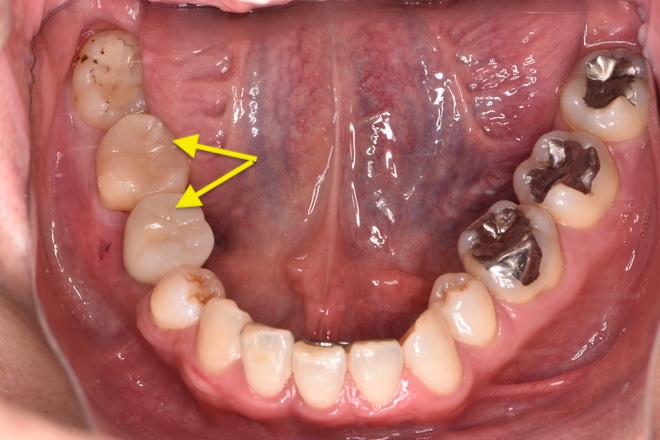

Case02下顎左右6番インプラント(マウスピース矯正を併用)

| 治療期間 | 6ヶ月 |

|---|---|

| 治療費 | インプラント2本1,100,000円 |

| 年齢・性別 | 20代女性 |

| リスクと副作用 | 腫れ、痛み、感染、神経損傷、将来的な脱落 |

| 備考 | 20代女性です。インプラント希望で来院されました。 他院でインプラントを入れるスペースがなく両方の歯を削る必要があると言われ、抵抗があるとのことでセカンドオピニオンで当院に来院されました。 赤坂さくら歯科クリニックオリジナルのインハウスアイライナーのサクライナー矯正で、隙間を閉じた上で一切削らずにインプラントを行いました。 患者様は隙間にものが挟まるストレスからも解放され、とても喜んでらっしゃいました。使用したインプラントはノーベルバイオケア社のインプラントになります。 大臼歯であっても細いインプラントを隙間を矯正などで調整しながら入れることが可能です。 |